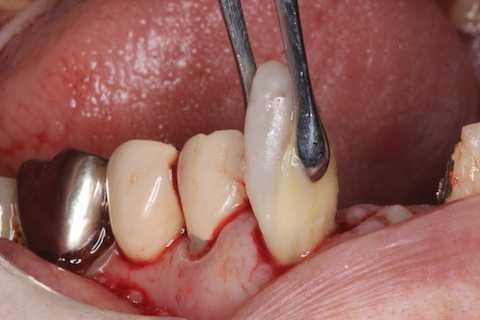

普通にズブズブと抜歯窩に再建した歯根を挿入する。

あとは接着固定しながら、歯冠を再建していく。